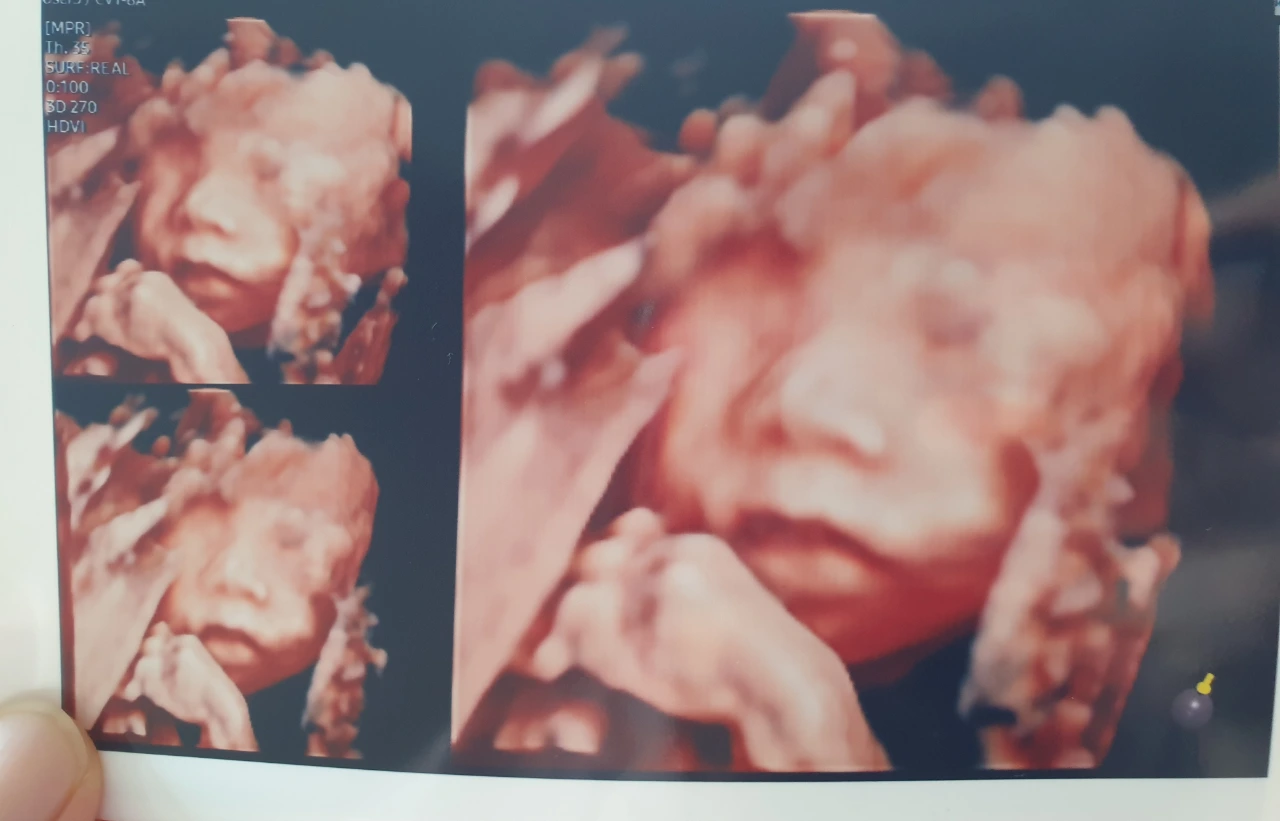

그래도 기다리는 동안 입체 초음파도 진행했는데 입체 초음파를 보니 걱정되었던 마음이 한시름 놓였다. 너무 귀엽고 사랑스러운 아이를 만나니 기분이 너무 좋았다. 이럴 수가! 나는 누굴 닮았다 라는 생각보다 너무 귀엽다 란 생각을 했는데, 보는 사람마다 남편을 닮았다고 한다. 남편은 시어머니를 꼭 빼닮았는데... 정말 유전자의 힘이 강한가?